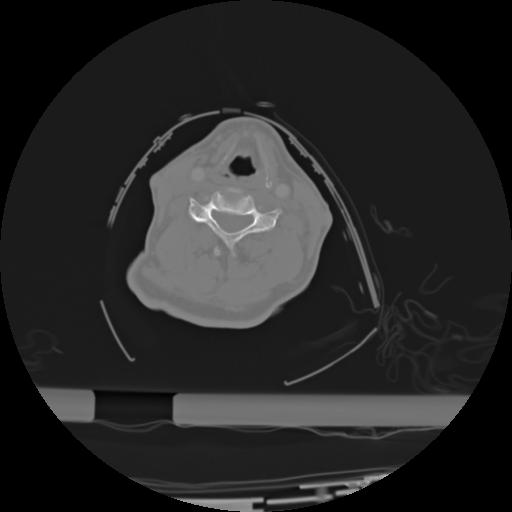

21 ANGIO,CE,Axial,3.0,ANGIO,,